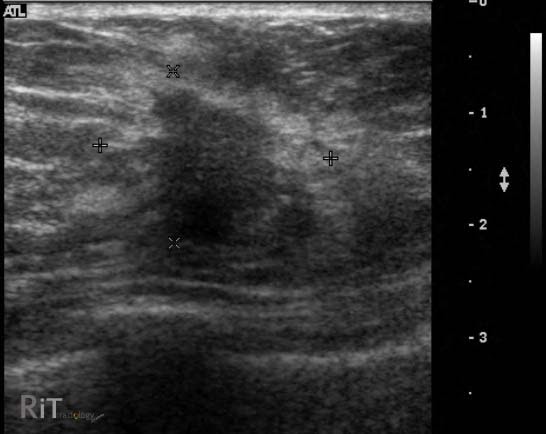

breast ultrasoundEl ultrasonido mamario es especialmente valioso para examinar mujeres con tejido mamario denso. Las mamas densas son menos transparentes a los rayos X de las mamografías y pueden ocultar tumores, lo que hace que el ultrasonido sea una opción complementaria importante. Al proporcionar imágenes detalladas del tejido mamario, el ultrasonido puede identificar masas y otras irregularidades que no son visibles en las mamografías. Detectar cáncer de mama en sus etapas iniciales es vital, ya que los tratamientos son generalmente más efectivos y menos invasivos cuando la enfermedad se descubre temprano.